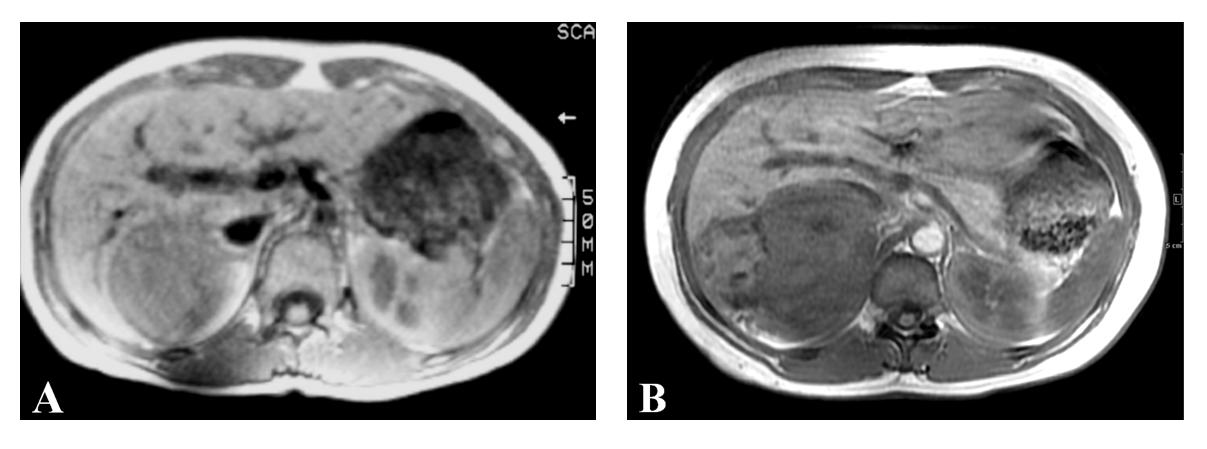

Laboratory studies revealed a serum cortisol level of 10.7 mcg/dL (normal 3-17), serum aldosterone of 2 ng/dL (normal 3-16), plasma renin of 1.46 ng/mL/h (normal 0.25-5.82) and serum metanephrines of 131 pg/mL (normal < 205) indicating that the tumor was non-functioning. MRI of the abdomen revealed a 14 cm, irregular, right adrenal mass with heterogeneous density and attenuation characteristics concerning for malignancy. Comparison with a previous MRI examination provided by the patient from 1992 revealed that the mass had slowly increased in size (from 6 cm to 14 cm) and changed in appearance over the period of 18 years (Fig. 1A, B). There was no evidence of metastatic disease seen to any lymph nodes, the liver, or the lungs.

![]() Click for large image | Figure 1. Serial MRI examinations spanning 18 years, showing low signal mass in the right adrenal gland which is irregular and heterogeneous on (A) Axial T1 spin echo measuring 6 cm in 1992 and (B) Axial T1 inphase gradient echo sequence measuring 14 cm in 2010. |